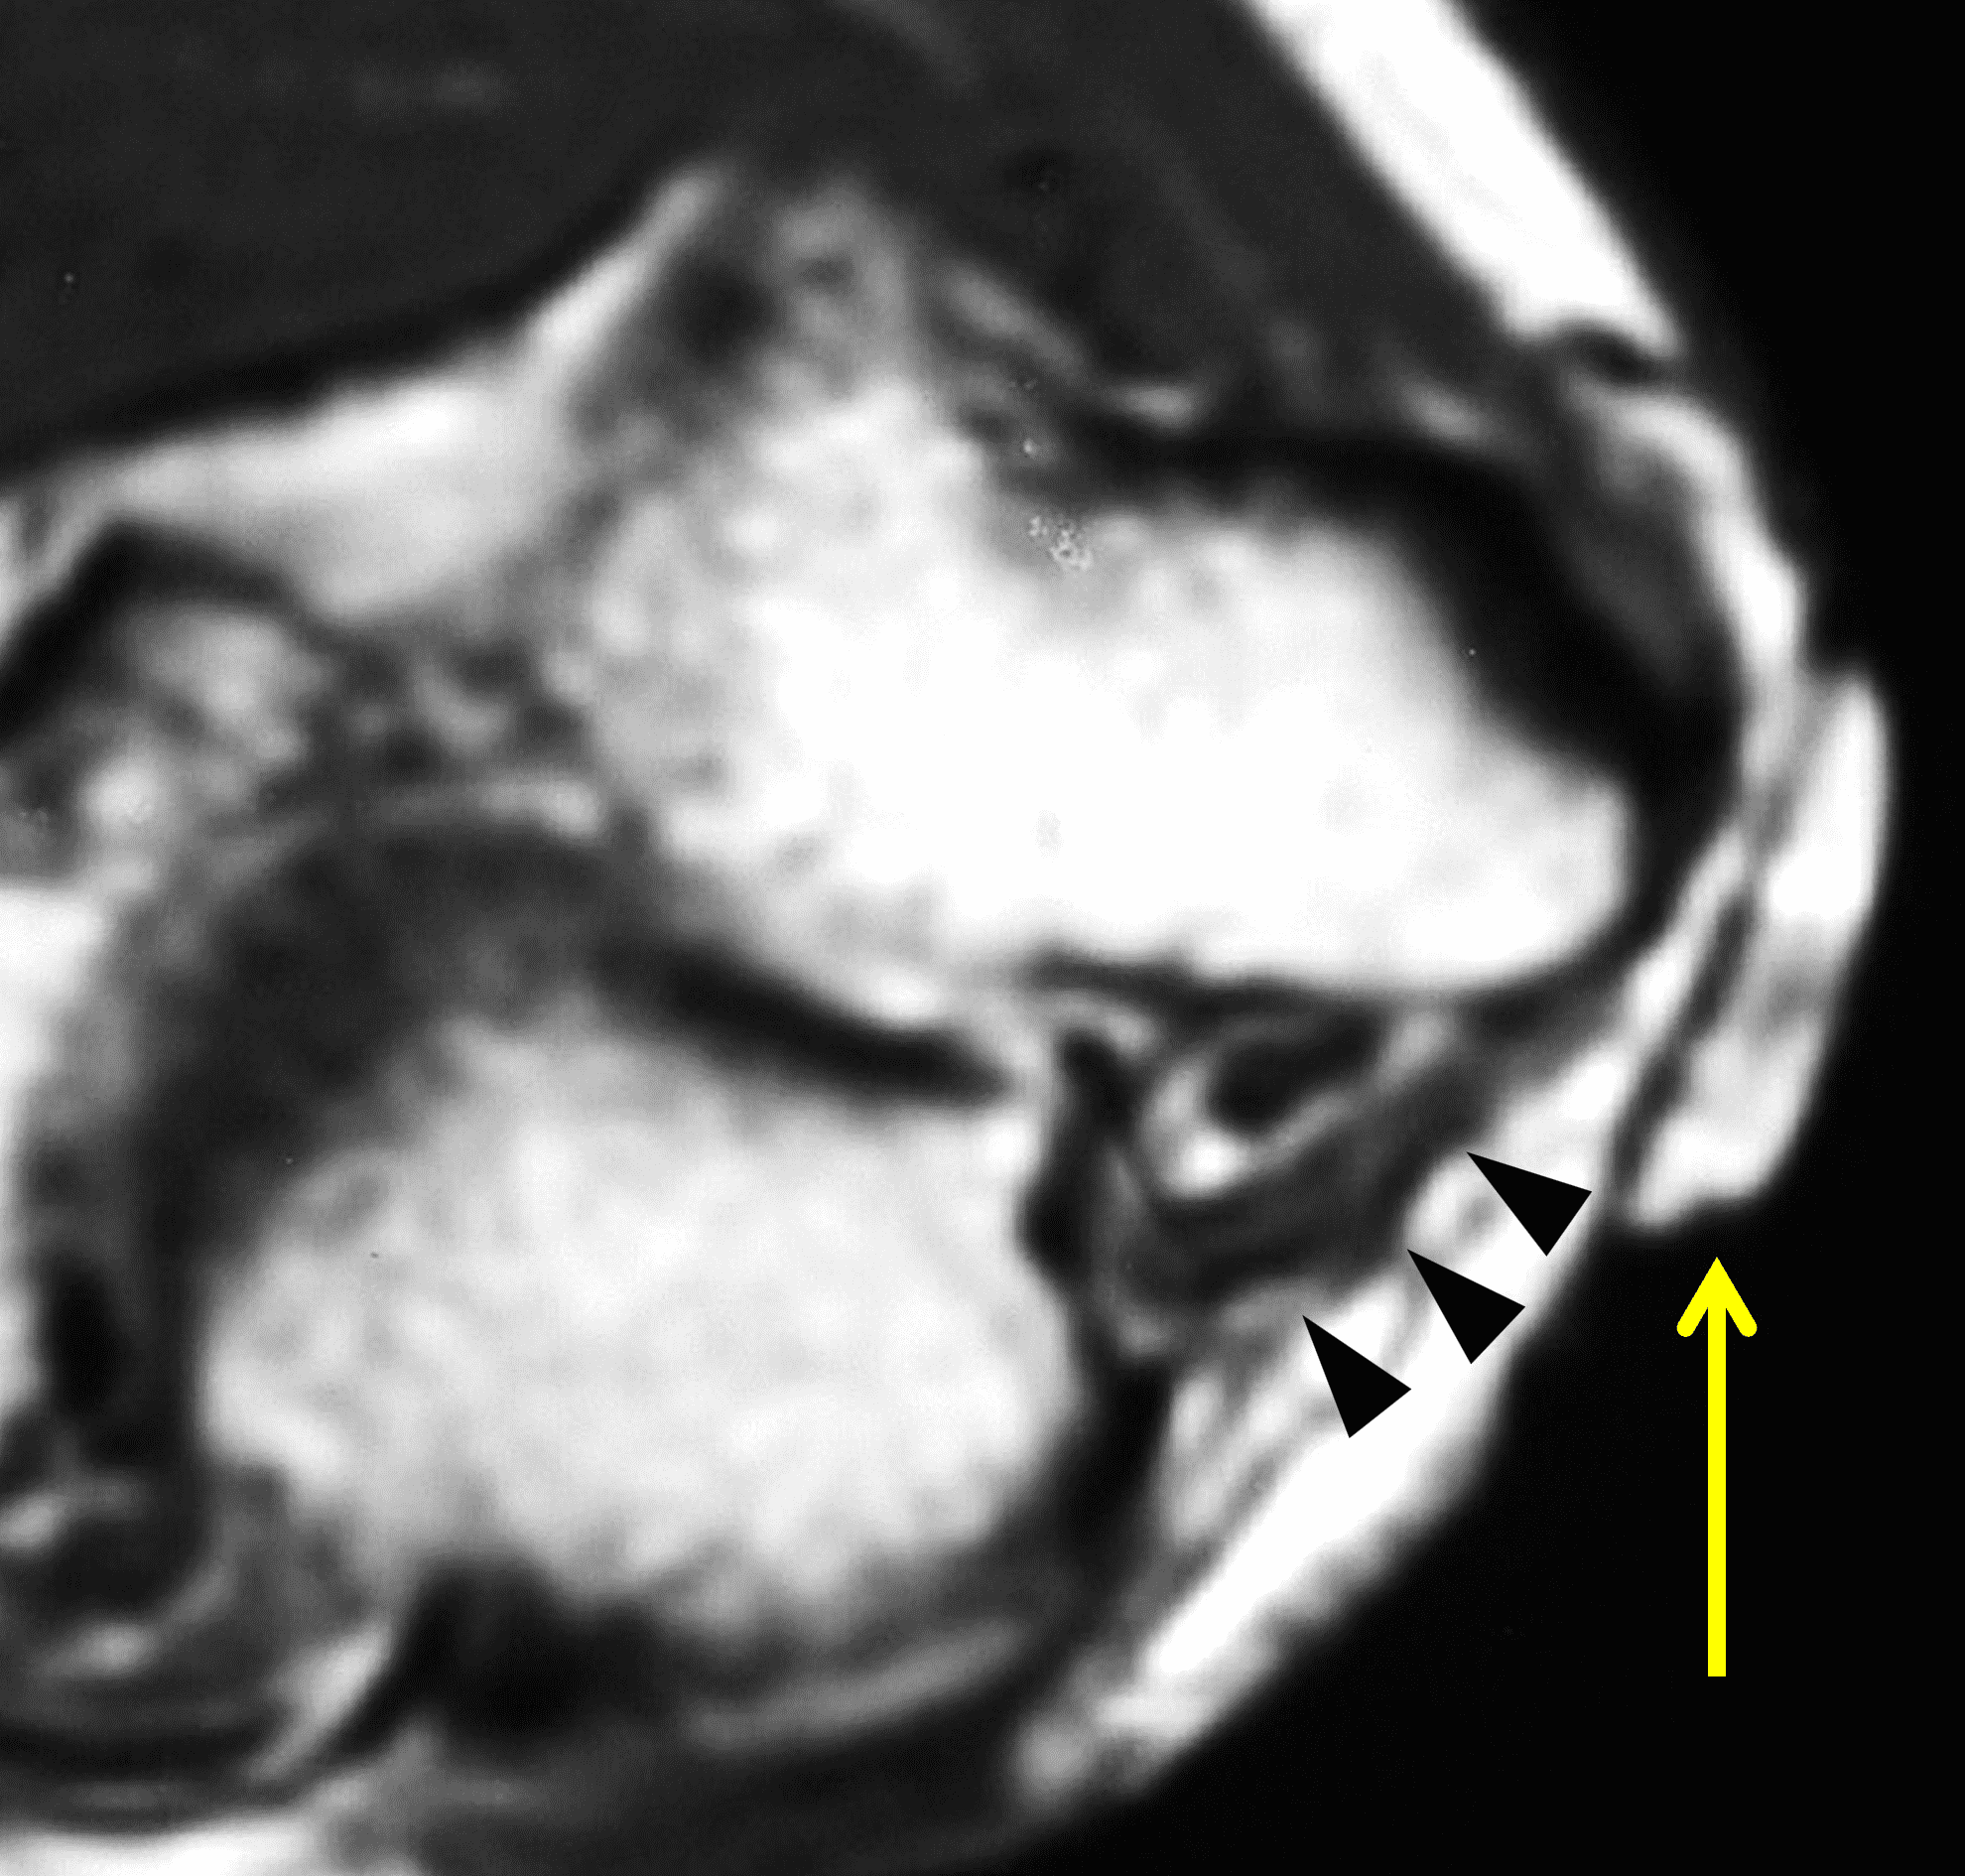

The ulnar nerve is susceptible to stretching, friction, and compression in the cubital tunnel. Normally with flexion, the cross-sectional area of the tunnel decreases as the overlying retinaculum becomes taut, increasing pressure within the tunnel. Additionally, the path that the nerve follows increases in length with elbow flexion, meaning that the nerve must be able to stretch and glide smoothly to prevent dysfunction.13 In some patients the nerve becomes flattened and compressed due to these physiologic changes during elbow flexion, resulting in ulnar neuritis and “idiopathic” cubital tunnel syndrome, which is similar to carpal tunnel syndrome where the median nerve in compressed without the presence of a space-occupying mass. Anatomic variations like a thick cubital tunnel retinaculum (Figure 5), a relatively distal insertion of the medial triceps muscle (Figure 6), or a shallow groove in the posterior medial humeral epicondyle may increase the likelihood of nerve compression. The cross-sectional area and volume of the cubital tunnel are smaller in patients with idiopathic cubital tunnel syndrome compared to controls, especially with elbow flexion.14

Figure 5: Thick cubital tunnel retinaculum. (5A) Drawing showing a thick retinaculum. Compare with Figure 3B. (5B) Axial T1-weighted image in a patient with clinical ulnar neuritis and a thick retinaculum (arrowheads) forming the roof of the cubital tunnel. This patient had a positive Tinel’s sign in the area localized by the placed marker (arrow).